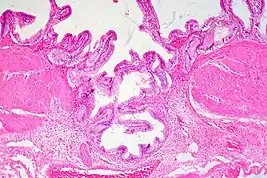

Gallbladder adenomyomatosis is a benign disease of the gallbladder characterized by hyperplasia of the mucosal epithelium and smooth muscle cells inside the muscularis propria.[4][5][6] The excessive proliferation of epithelial cells causes the mucosa to invaginate into the muscular layer lining the gallbladder wall, resulting in characteristic diverticula known as Rokitansky-Aschoff sinuses. These sinuses may be filled with biliary sludge, cholesterol crystals, or gallstones.[4][5][6]

There are three morphologic variants described in the literature – diffuse, segmental, and localized.[5][6] Diffuse, also known as generalized, adenomyomatosis has a widespread distribution of hyperplastic changes and thickening across the gallbladder wall.[5][6] The localized form of adenomyomatosis is also known as a gallbladder adenomyoma (in a similar manner that uterine adenomyoma is the localized variant of adenomyosis). The localized form is a single mass, typically in the fundus, that protrudes into the lumen of the gallbladder in the form of a polyp.[5][6] The segmental form is characterized by its annular (ring-shaped) distribution of adenomyomatosis in the body of the gallbladder, often giving it an hourglass-like appearance.[5][6]

Ultrasound is the preferred initial diagnostic choice for suspected gallbladder disease. Several distinct features of adenomyomatosis are discernable using ultrasound, making it a reliable modality for diagnosis.[4][5][6] The most characteristic features seen on ultrasound are the Rokitansky-Aschoff sinuses, which present either as echogenic foci when filled with biliary sludge/gallstones or anechogenic foci when filled with normal bile.[4][5][6] Other key features that may be seen include wall thickening and ring-down artifacts known as "comet tails" (produced by reverberations of sound between the sinuses).[4][5][6] Ultrasound can also distinguish between diffuse, segmental, and localized variants of adenomyomatosis based on morphology.[5][6]

In some cases, gallbladder wall thickening may be seen on ultrasound but is poorly defined and lacking specificity, particularly if the characteristic Rokitansky-Aschoff sinuses are not visualized. This can make it difficult to distinguish adenomyomatosis from other conditions that result in gallbladder wall thickening such as gallbladder cancer.[4][5][6] In these cases, MRI can prove helpful in providing the resolution needed for diagnosis. Especially effective is the T2-weighted MRI at visualizing the pathognomonic Rokitansky-Aschoff sinuses, which appear as round-shaped hyperintense cystic spaces that align in a curvilinear fashion along the gallbladder wall in a pattern described as the ”pearl necklace sign”.[4][5][6]